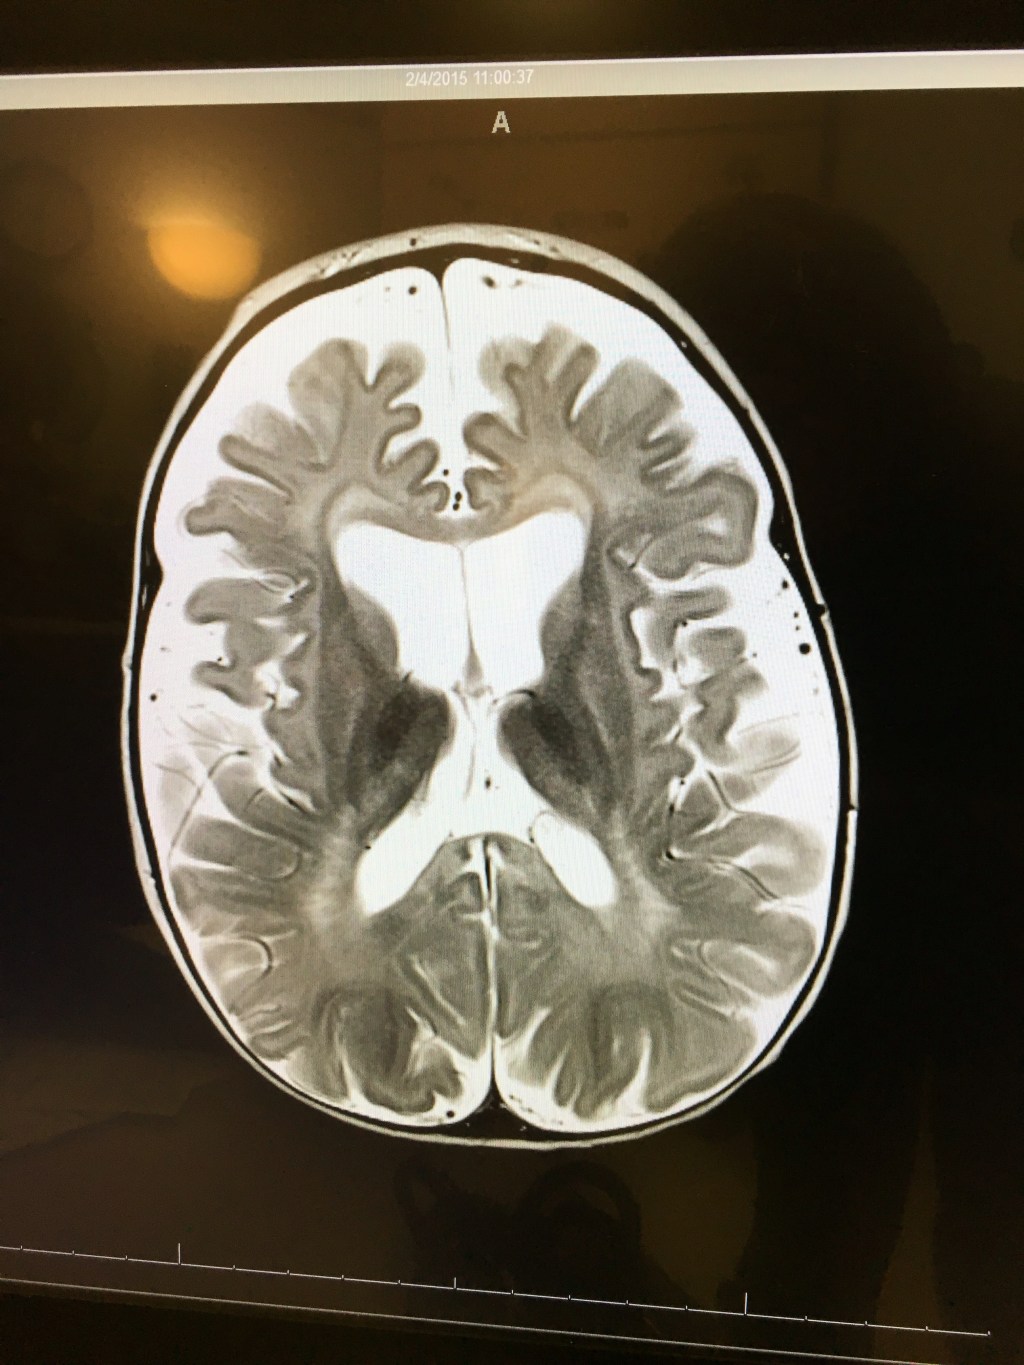

She also showed us an image of Tori’s current MRI so we could compare it to the one from last year:

Last year:

Unfortunately, her brain has continued to atrophy and Krabbe is still very present. But, God is sovereign and still in control!